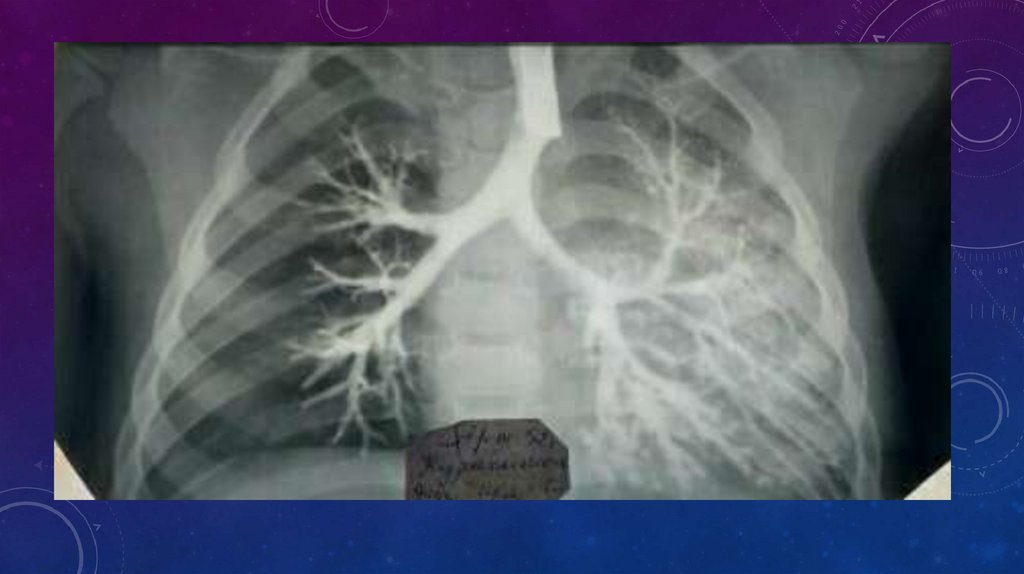

• Бронхографию, особенно у детей, следует выполнять водорастворимыми контрастными веществами,

поскольку они всасываются и быстро выводятся из организма. Масляное контрастное вещество (йодолипол),

наоборот, может длительно задерживаться в легочной ткани не только в пораженных, но и в здоровых

участках легкого.

• Наиболее целесообразна методика бронхографии над наркозом с искусственной вентиляцией легких.

Дыхание осуществляют через интубационную трубку или с помощью дыхательного бронхоскопа.

Контрастное вещество вводят во время апноэ по катетеру, который постепенно подтягивают от

нижнедолевого к верхнедолевому бронху. Первый снимок производят в положении на исследуемом боку,

второй — в положении на спине. После тщательной аспирации контрастного вещества из бронхов

приступают к контрастированию второго легкого.

• Для правильной интерпретации бронхограмм необходимо ориентироваться в сегментарном строении

легкого и картине разветвлений бронхиального дерева. Наиболее информативны бронхограммы в боковых

проекциях, на которых хорошо видны все долевые и сегментарные бронхи. В норме бронхи заполняются

контрастным веществом, вплоть до терминальных разветвлений, при этом они равномерно суживаются к

периферии и имеют ровные, гладкие контуры. При бронхоэктазии на бронхограммах выявляются

деформации бронхиального дерева: цилиндрические и мешковидные расширения бронхиальных стволов,

без контрастирования терминальных отделов. В зонах ателектаза и склероза бронхи особенно

деформированы и сближены.